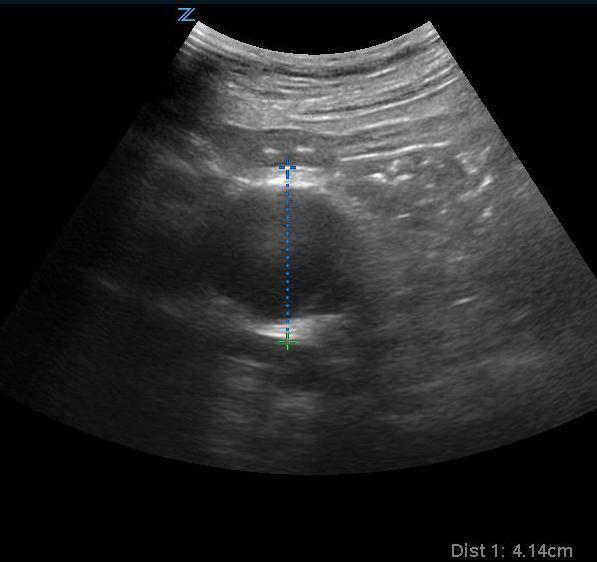

- Figure 7. Transverse view of a 4.1 cm AAA

Video 4. Transverse view of large AAA